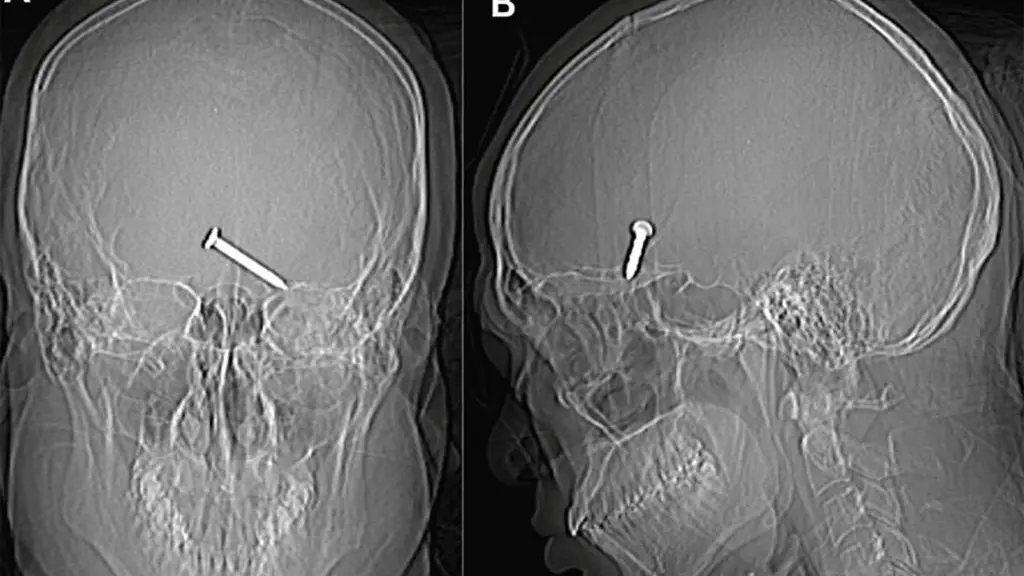

Stunning X-ray images reveal a 3.2 cm nail deeply lodged in the frontal lobe of the man's brain which is a critical region for movement and speech. The bleeding had extended to other areas of his brain. The study, published in the medical journal, reports wounds at the lateral canthus of the left eye where the two eyelids meet, along with fractures of the left orbital roof and floor. Remarkably, the nail managed to avoid crucial arteries and nerves, sparing the man from any enduring damage, as indicated in the study.